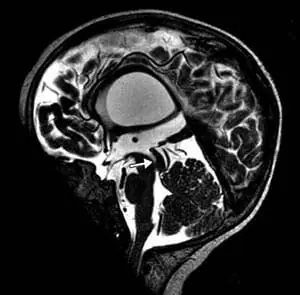

頭部磁気共鳴映像法では、テント上水頭症、視交叉陥凹のバルーニング、薄い脳梁、側脳室および第3脳室の拡張、透明中隔の欠如、および脳の低髄鞘化が明らかになった(図2)。

図2. 磁気共鳴画像法T2強調矢状画像。 脳梁は薄かった。 磁気共鳴画像法T2強調冠状断像。